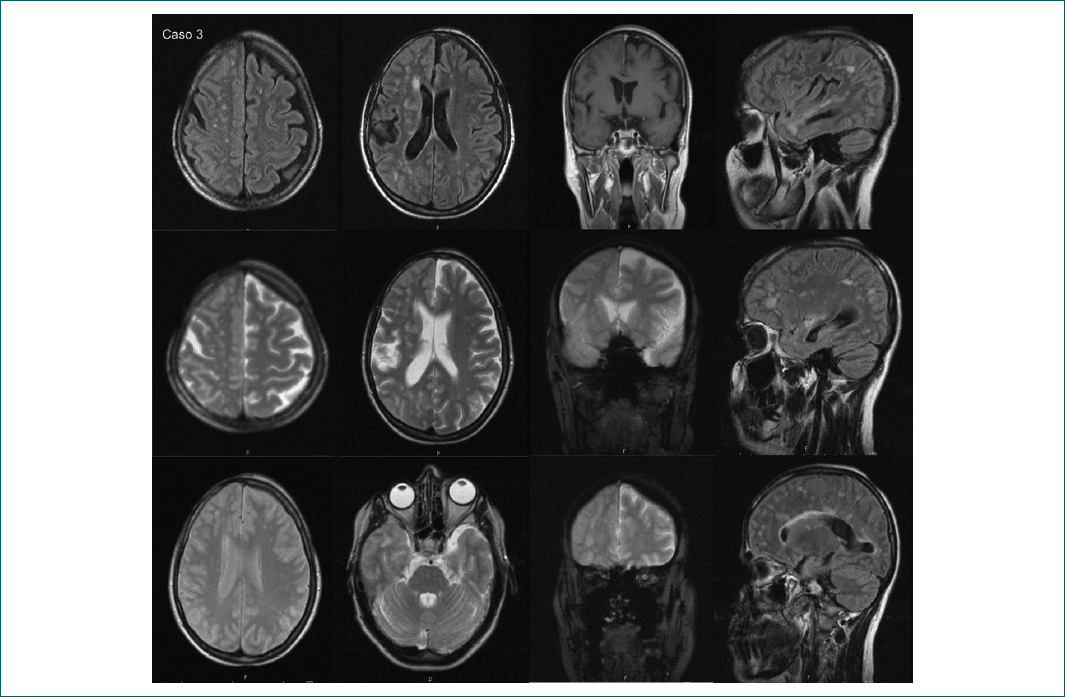

Mujer de 36 años cuyos síntomas comenzaron a los 4 años con una mancha hipocrómica en la región facial frontal derecha, que evolucionó con hundimiento lineal y alopecia. Se diagnosticó como esclerosis en golpe de sable. Recibió dapsona y griseofulvina (se desconocen las dosis) hasta los 14 años, y los síntomas progresaron con una zona de hipercromía en la región mandibular, esclerosis dérmica, deformidad ósea y atrofia hemifacial homolateral, tratada con prednisona (PD), suspendida por síndrome de Cushing. La TC y la RM (Fig. 2) mostraron lesión parenquimatosa y datos compatibles con vasculitis en el SNC, por lo que se concluyó que se trataba de un SPR. La paciente evolucionó con extensión ocular derecha (refirió dolor ocular y disminución de la agudeza visual monocular, sin datos de neuritis en la exploración oftalmológica; en la RM se observó el globo ocular retraído y el nervio óptico plegado) y cefalea hemicraneana incapacitante sin respuesta a los analgésicos. Presentó ANA de 1:80 (nucleolar y segunda determinación con moteado fino). Los anticuerpos anti-DNA y ANCA fueron negativos, y la proteína C reactiva fue de 3.14. Se inició tratamiento con MPD (1 g mensual por 6 meses), seguido de PD (15 mg/día) y de metotrexato (MTX) (10 mg a la semana), con aparente estabilización y posterior recaída, por lo que se reinició tratamiento con MPD y CFM (1 g mensual por 6 meses, seguido de dosis bimensual hasta 12 dosis), con MTX como mantenimiento, a pesar de lo cual en el seguimiento persistió con cefalea de difícil manejo. El tratamiento quirúrgico incluyó colocación de placa por disfunción temporomandibular, lipoinyecciones en cuatro ocasiones, rinoplastia e injerto de cabello.